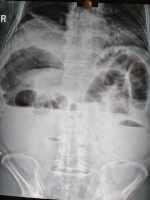

腸切除+腸吻合術治療壺腹癌術后絞窄性腸梗阻1例 關鍵疾?。?a href="http://m.akellydesign.com/tags/so/壺腹癌術后,絞窄性腸梗阻,-4-1.html" target="_blank">壺腹癌術后,絞窄性腸梗阻, 現(xiàn)病史【一般資料】 男性,64歲,農民 【主訴】 壺腹癌術后半個月,腹痛,惡心、嘔吐,腹脹,停止排氣排便3小時。 【現(xiàn)病史】患者家屬訴緣于半月前于外地醫(yī)院行壺腹癌手術,術后恢復良好,正常排氣、排便,無發(fā)熱、腹痛,無惡心、嘔吐、腹脹。3小時前無明確誘因出現(xiàn)腹部疼痛,為持續(xù)性鈍痛,陣發(fā)性加劇,以右上腹為重,無他處放射,伴惡心、嘔吐2次,嘔吐物為血性物,不含蛔蟲,共吐約800毫升左右,吐后腹痛未減輕,伴右上腹局限性隆起,排氣排便停止。無發(fā)冷、發(fā)熱,無心慌氣短,無咳嗽咳痰,無尿頻、尿痛及肉眼血尿,無四肢厥...

闞***軍 | 主任醫(yī)師 外科 普外科 瀏覽:3365